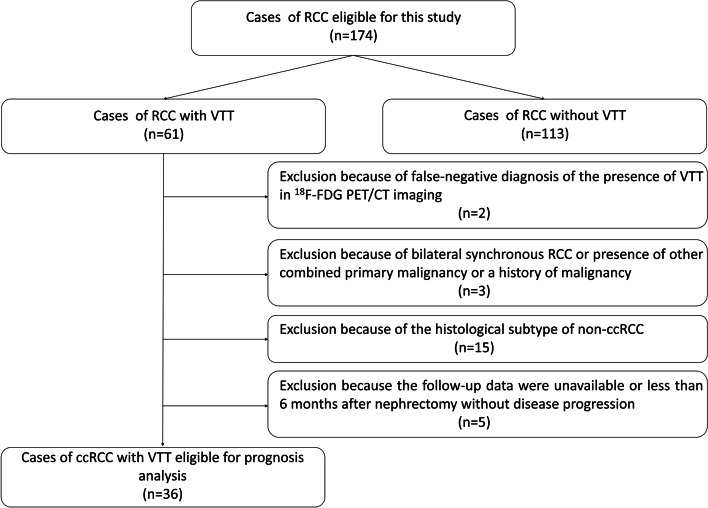

The inclusion criteria were as follows [15–17]: (1) newly diagnosed RCC by primary tumor pathological analyses, (2) radical nephrectomy or combined with tumor thrombectomy (for patients with VTT) performed at our hospital, and (3) 18F-FDG PET/CT performed before operation and systematic treatment initiation. The additional inclusion criterion for prognosis analysis was available follow-up data for more than 6 months after operation for the patients without disease progression. The additional exclusion criteria for prognosis analysis were as follows: (1) patients with false-negative diagnosis of presence of VTT in 18F-FDG PET/CT imaging, (2) patients with histological subtype of non-ccRCC, (3) patients with presence of other combined primary malignancy or a history of malignancy including RCC, and (4) patients with bilateral synchronous RCC. The flow diagram of the inclusion and exclusion of patients is presented in Fig. 1.

Fig. 1.

The flow diagram about the inclusion and exclusion of patients